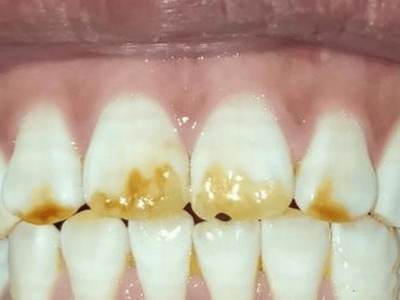

牙齿

黄斑

牙釉质发育不全牙齿黄斑图

牙釉质发育不全患者的牙齿表面出现淡黄斑,呈条纹状或不规则状,导致牙齿看起来有些脏污,患者无自觉不适,牙齿功能正常,建议到口腔科就诊,恢复牙齿外观。